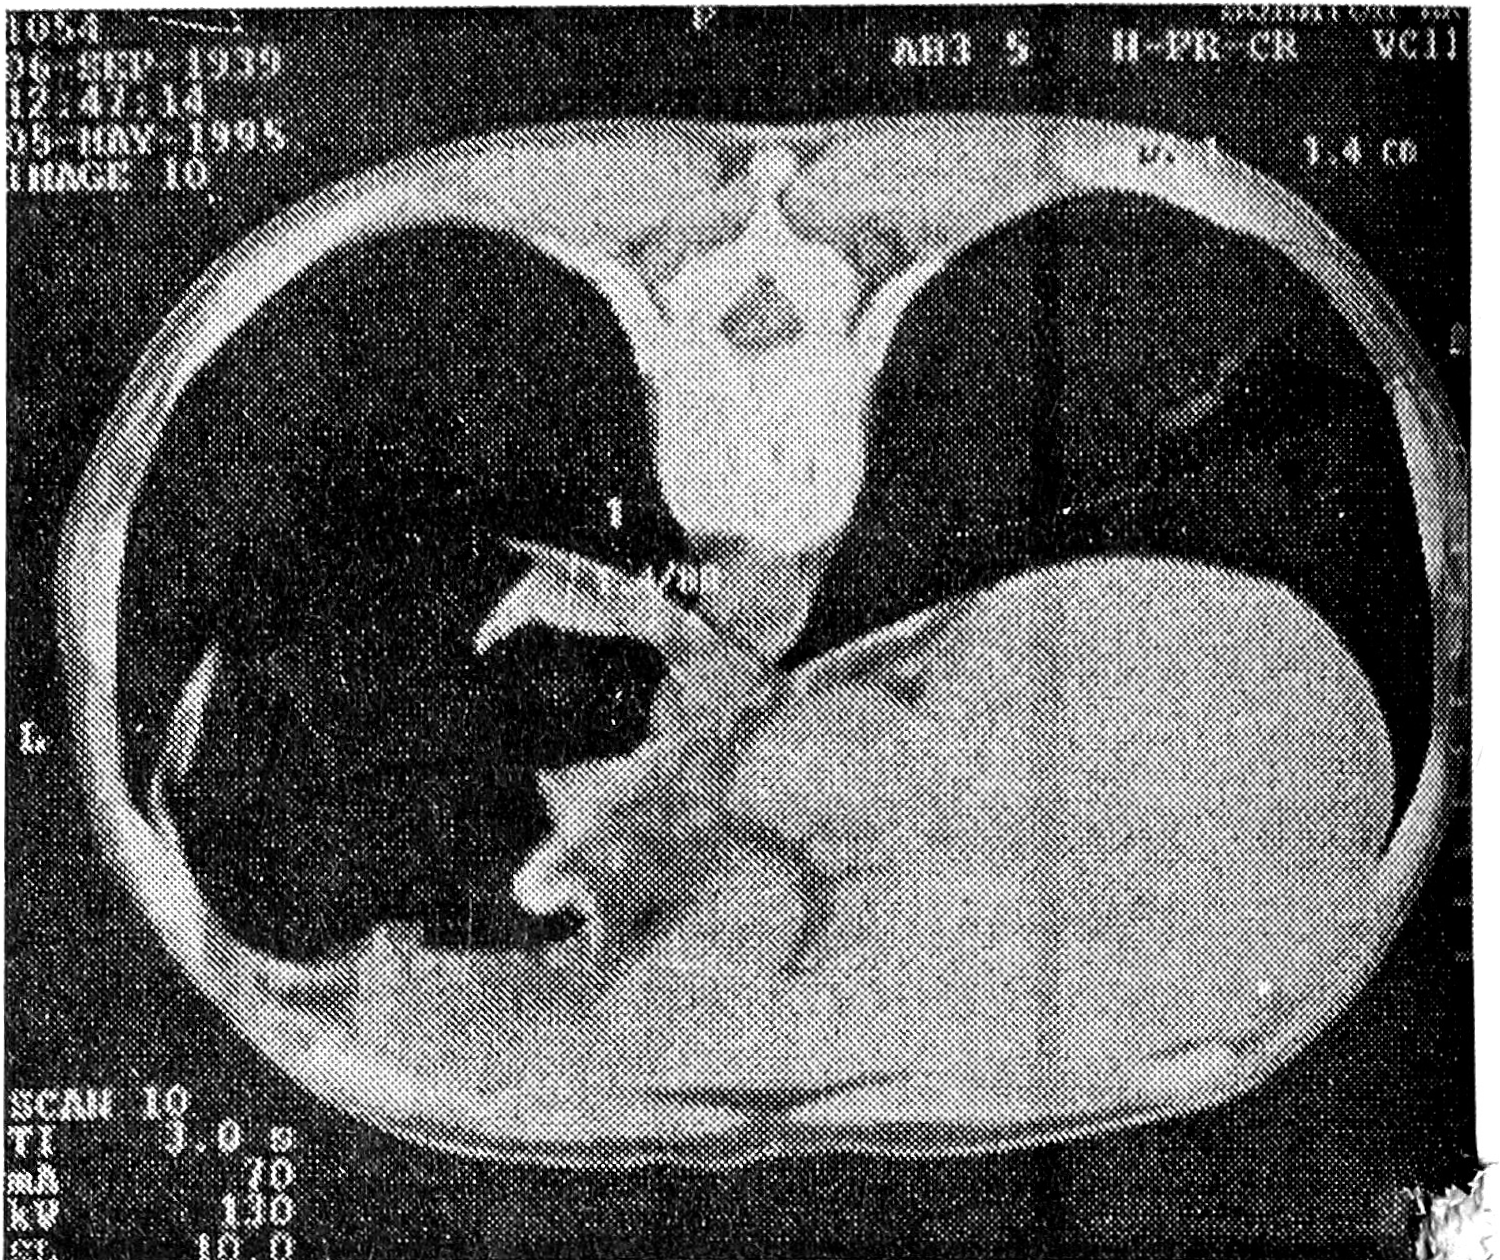

Исследование показало, что основным КТ-признаком эндофитного рака желудка можно считать утолщение его стенки в месте опухолевого поражения до 1 см и более (рис. 1). При опухолях небольших размеров (до 4-5 см) это утолщение носило локальный, ограниченный характер. Распространения процесса за пределы стенки желудка на соседние структуры не наблюдалось. Контур поражения был ровный, эластичность стенки нарушалась незначительно (рис. 2, 3). Отчетливую границу между пораженным участком и неизмененной стенкой желудка провести было трудно. При КТ-диагностике сравнительно небольших по размерам эндофитных опухолей желудка (вызывающих затруднения как при классическом рентгенологическом, так и при эндоскопическом исследованиях) необходимым условием являлась сравнительная оценка толщины стенки желудка на ограниченных участках с соседними неизмененными участками. Даже незначительное утолщение ограниченного участка стенки (до 7-8 см) при наличии других рентгено-эндоскопических признаков эндофитного поражения являлось дополнительным критерием, подтверждавшим эндофитный рак желудка. К достоинствам КТ необходимо отнести возможность обнаружения в процессе исследования гионарных и отдаленных метастазов, которые встречались достаточно часто даже при небольших по размерам опухолях желудка.

Рис. 2. КТ желудка больной М., 70 лет. Небольшой эндофитный рак антрально-препилорического отдела желудка. Определяется утолщение стенок этого отдела желудка до 1,4 см с довольно ровными контурами.